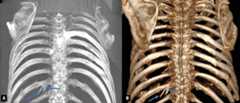

Srb anomaly prevalence was found as 0.27%. Three (1.36%) cases had SRB anomaly, and the mean age 50.33.All the cases were male. All SRB anomalies were unilateral;1was on the right side, while2were on the left (Fig. 4).

Figure 4.Cases with the right (A) and left (B) Srb anomaly.